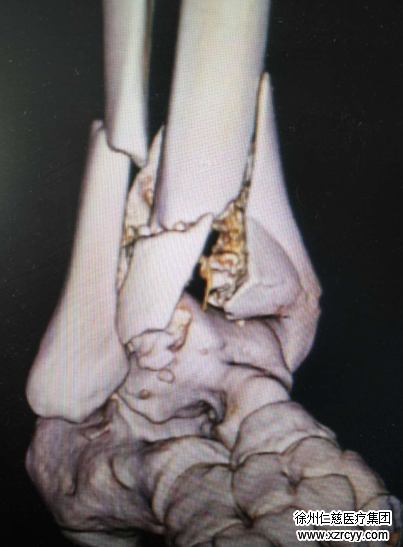

当天,足踝外科是袁罕医生坐诊,袁医生询问了病因,检查发现刘大强的双小腿远端肿胀明显,压痛明显,左小腿远端外翻畸形,甚至轻轻一触就能听到小腿远端骨头摩擦的声音,双足前端反应迟钝、麻木。CT扫描显示双胫腓骨远端骨折,双跟骨骨折、距骨骨折,腰椎椎体骨折。看似不太重的一跤,摔出的后果却如此严重!

术中,手术团队聚精会神,分工协作,先进行右踝关节骨折的复位及内固定。在右外踝侧做10厘米长切口,见关节粉碎严重,予以手法复位腓骨远端骨折端,六孔钢板固定;小腿远折端粉碎严重,关节面消失,复位骨折块,克氏针固定,手法复位关节面,克氏针固定,L型锁定钢板固定;右踝后内侧切6厘米长切口,手法复位粉碎骨折端,克氏针固定,钢板固定。同样的方法,在左踝关节的前侧、内侧分别手法复位骨折端,克氏针固定,L型钢板固定。

手术进行了漫长的5小时35分钟,两侧小腿远端共作了4切口打了7块钢板。参与手术的袁医生说:“手术时间特别长,对体力要求很高,赵博士和我院团队合作的这台手术做得非常好。pilon骨折碎成这样的非常少见,手术难度比较大,这种双pilon骨折后期是有致残风险的,手术做得好的话风险则会大大降低。”